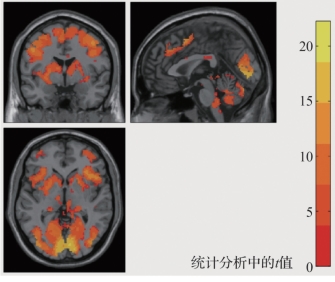

对任务态fMRI数据的分析和处理,首先需要确定与任务对应的激活区。其次是对激活区内部的时间序列曲线的变化情况进行分析,以研究各个激活区活动期间的信号变化情况,最终得到各个功能区之间的相互关系,包括空间关系和时间关系。研究者目前一般都使用SPM或AFNI软件,这两个软件都可以使研究者很方便地基于广义线性模型来分析和处理任务态fMRI数据。研究者需要提供给软件的是设计矩阵,然后使用SPM或AFNI软件就可以很方便地估计出控制变量的效应大小,进而找到受控制变量影响的脑区,即和任务刺激相对应而激活的脑区。图5.18为SPM绘制的赌博任务激活脑区的示意图。

图5.18 SPM绘制的赌博任务激活脑区的示意图(书后附彩插)